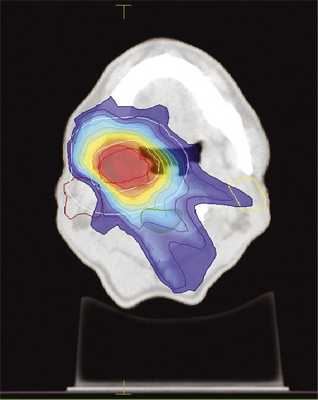

Больной Е., 1957 года рождения, проходил лечение в клинике МРНЦ им. Цыба в июне 2013 г. с диагнозом: плоскоклеточный рак ротоглотки (небная миндалина справа) cT2N0M0. Проведен радикальный курс одновременной химиолучевой терапии, в конвенциональном режиме РОД 2 Гр до СОД 60 Гр. После окончания лечения достигнута полная регрессия опухоли, однако через 1 год он вновь обратился в клинику с рецидивом образования миндалины. При обращении у больного имелись осложнения предшествующего лечения в виде ксеростомии 1—2-й степени и тризма 1-й степени. Проведен курс повторной конформной лучевой терапии в режиме гипофракционирования РОД 3 Гр до СОД 48 Гр, с одновременной химиотерапией (цисплатин + 5-фторурацил). Методика IMRT в данном случае позволила практически полностью исключить из поля облучения височно-нижнечелюстные суставы и большие слюнные железы (рис. 2), поскольку после проведения реконструкции ранее полученных доз облучения органов риска было выявлено их превышение (табл. 2). Острые лучевые реакции во время повторного облучения проявились в виде мукозита 2-й степени. В настоящее время больной наблюдается в течение 1 года без признаков рецидива и усиления лучевых повреждений.

Рис. 2. Дозное распределение при повторном облучении очага в носоглотке методикой IMRT. Градиентом цвета обозначен переход от максимальной дозы (красное) к минимальной (синий цвет, 10% от максимальной). Покрытие мишени (PTV) не менее 95%.